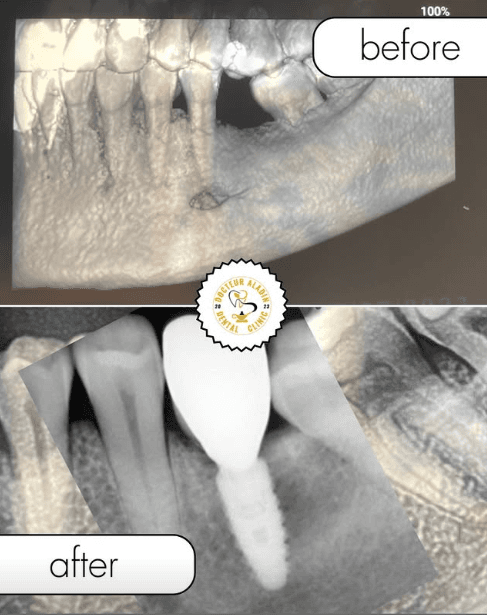

Before / After Results

Découvrez les transformations de nos patients